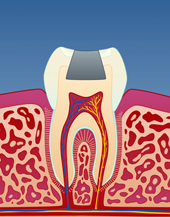

I tenner med store fyllinger, er tannsubstansen rundt fyllingen svekket. Når man tygger, kan det etter hvert utvikles tynne sprekker i tannen. Disse sprekkene utvikler seg under fyllingen og forløper vanligvis på skrå bort fra tann-nerven. Over tid kan slike sprekkdannelser medføre at en del av tannen knekker og faller ut. I noen tilfeller knekker tannen fordi man tygger på noe hardt, men ofte er dette ikke tilfelle. Det er heller den totale belastningen over tid som er utslagsgivende og tidspunktet for tannfrakturen er ofte tilfeldig.

Tenner som er rotfylt, eller som er under rotfyllingsbehandling, er særlig utsatt for å knekke. Slike tenner har ofte hatt store og dype hull som er reparert med fyllinger. Derfor vil den gjenstående tannsubstansen være svekket. Når tannen skal rotfylles, må det i tillegg lages en åpning inn til nerven som vil medføre en ytterligere svekkelse av tannen. Man ser også at tannen ”tørker ut” når nerven er renset bort, noe som kan bidra til en utvikling av allerede eksisterende sprekkdannelser.